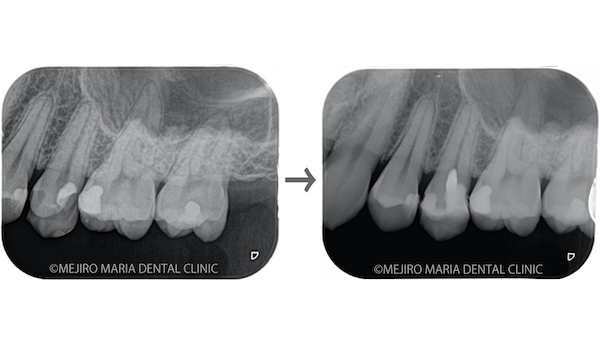

【症例】生活歯保存療法(生活歯髄療法)による歯髄保存症例(精密根管治療)

• 目白マリア歯科0125生活歯髄切断法を用いた歯の神経の保存症例レントゲン写真